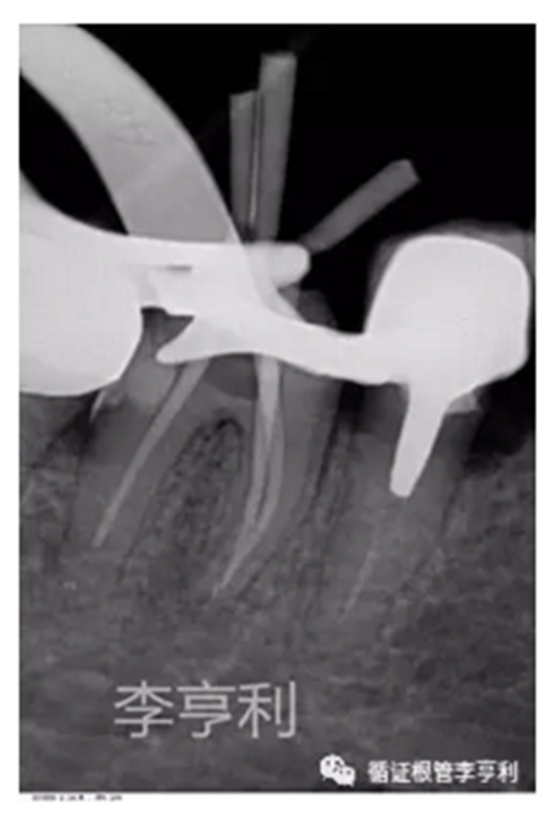

暴露器械斷端 (2017-06-26)

器械被超聲震出 (2017-06-26)

【治療過程】:由于患者根管系統(tǒng)較細窄,無法建立旁路疏通MB根,因此決定取出分離的器械。首先在顯微鏡下暴露器械斷端,然后使用超聲工作尖震動斷針,30分鐘內(nèi)斷針被順利震出,然后疏通MB到根尖。之后就常規(guī)完成剩余根管治療步驟,轉回進行后續(xù)冠修復。